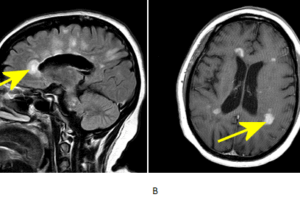

Tumefactive MS on MRI

Tumefactive multiple sclerosis

Tumefactive multiple sclerosis (MS) is an unusual but important manifestation of multiple sclerosis. Read more »